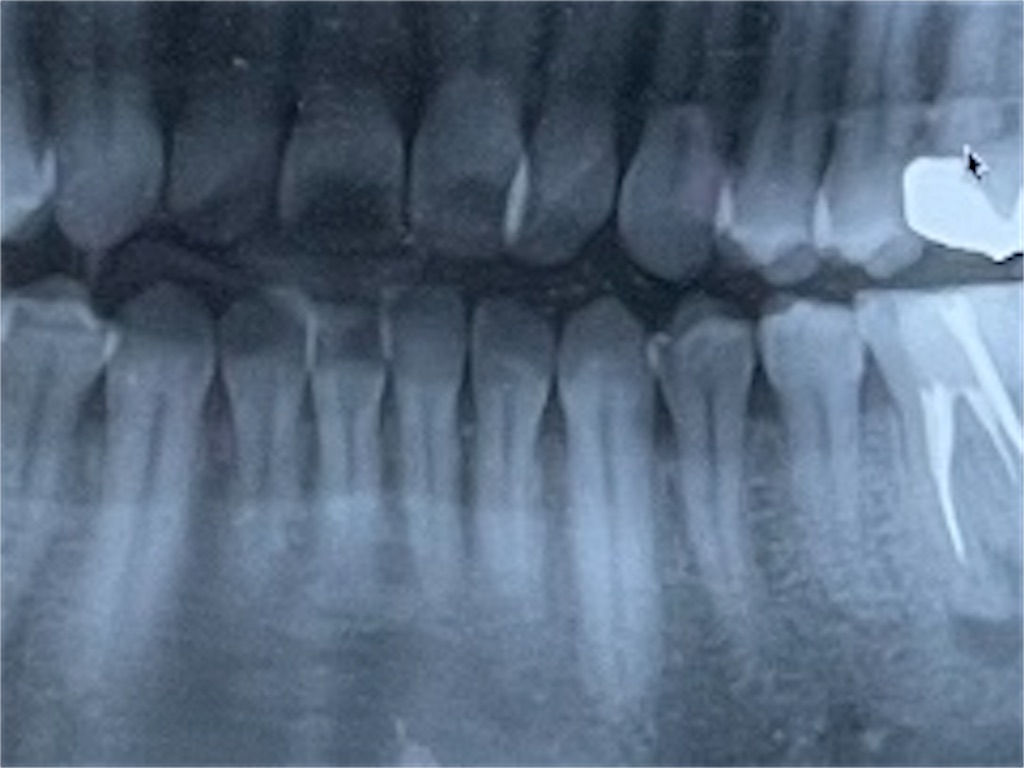

▲今回の詰め物と関係ないけど、下の歯を見ておくれ

この歯も神経を取り除いているのだ。痛いのは嫌なのだ。

なんか3つぐらい差し込まれている。これは感染症を防ぐ薬なんだそうだ。

下の奥歯の神経抜いた薬を打ち込んだ下側を見てみ

黒いところ。

歯医者「感染してますね。」

感染しているそうで、治療を早くしてねととです。